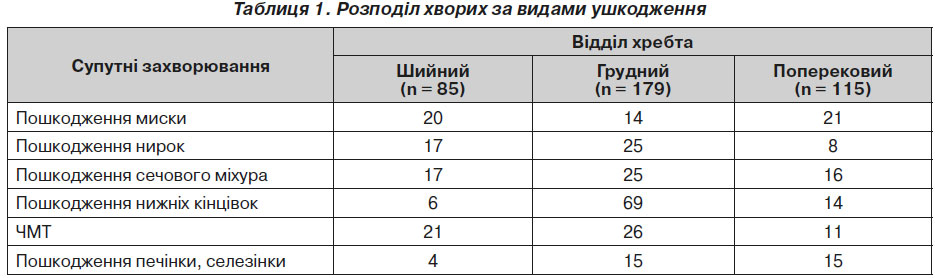

Хворі були розподілені на групи за типом ушкоджень: сегментів хребта, органів черевної порожнини, опорно-рухового апарату та черепно-мозкова травма (ЧМТ) (табл. 1).

21 пацієнту з чіткою картиною пошкодження спинного мозку проводилося хірургічне втручання: у перші 6 годин — 9 хворим, упродовж 24 годин — 8, 4 хворим хірургічне втручання було здійснене через 5 днів. При травмі шийного відділу хребта у хворих були виявлені пошкодження нирок, органів черевної порожнини, печінки, селезінки та кінцівок, ЧМТ (табл. 1).